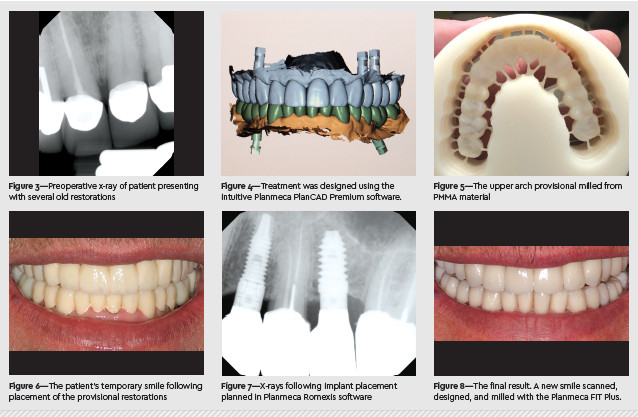

A 64-year-old male presented with several old restorations that showed significant deterioration. He was unhappy both with the appearance and function of his dentition. I suggested we remove the old bridges and crowns and start anew, telling him, “We can’t just do 1 or 2 teeth. You have so much dentistry that’s been done that we basically need to re-equilibrate your bite and give you a comprehensive design for a nice, new smile. You’ll look so much younger and brighter.” After creating a smile design and showing him images of what he could look like, he said, “You know what? If you can deliver that type of work, then I’m in.” We decided to move forward with a full-mouth rehabilitation involving 28 single-unit zirconia crowns. For the 5 edentulous sites—3 maxillary and 2 mandibular—where the bridges had been, we would place 5 implants (BTI) with custom abutments and screw-retained crowns. We assessed bone quality using a cone-beam scan and designed both the temporary and permanent restorations using the intuitive Planmeca PlanCAD Premium software. Treatment began with significant prep and refinement, digital impressions with the Planmeca Emerald S, and immediate placement of esthetic PMMA temporaries, which were milled using the Planmeca PlanMill 50 S.

Prosthetic-driven implant planning was completed in Planmeca Romexis software, and the patient returned for implant surgery, followed by a healing period of 3 months. During the final appointment, we placed all 28 individual teeth, which had been milled in the Planmeca PlanMill 50 S using IPS e.max ZirCAD Prime (Ivoclar Vivadent).

Afterward, the patient was very pleased, telling me, “Thank God for modern dentistry, because I never thought this would be possible.” In years past, this would have been a longer process with Figure 3—Preoperative x-ray of patient presenting with several old restorations Figure 4—Treatment was designed using the intuitive Planmeca PlanCAD Premium software. Figure 5—The upper arch provisional milled from PMMA material Figure 6—The patient’s temporary smile following placement of the provisional restorations Figure 7—X-rays following implant placement planned in Planmeca Romexis software Figure 8—The final result. A new smile scanned, designed, and milled with the Planmeca FIT Plus. extensive lab communication, wait time, and myriad potential problems with timeconsuming solutions. This patient wanted everything done in one shot, with as few appointments as possible, and we were able to accommodate him by designing and delivering his new dentition in-house, from start to finish, in 5 months.